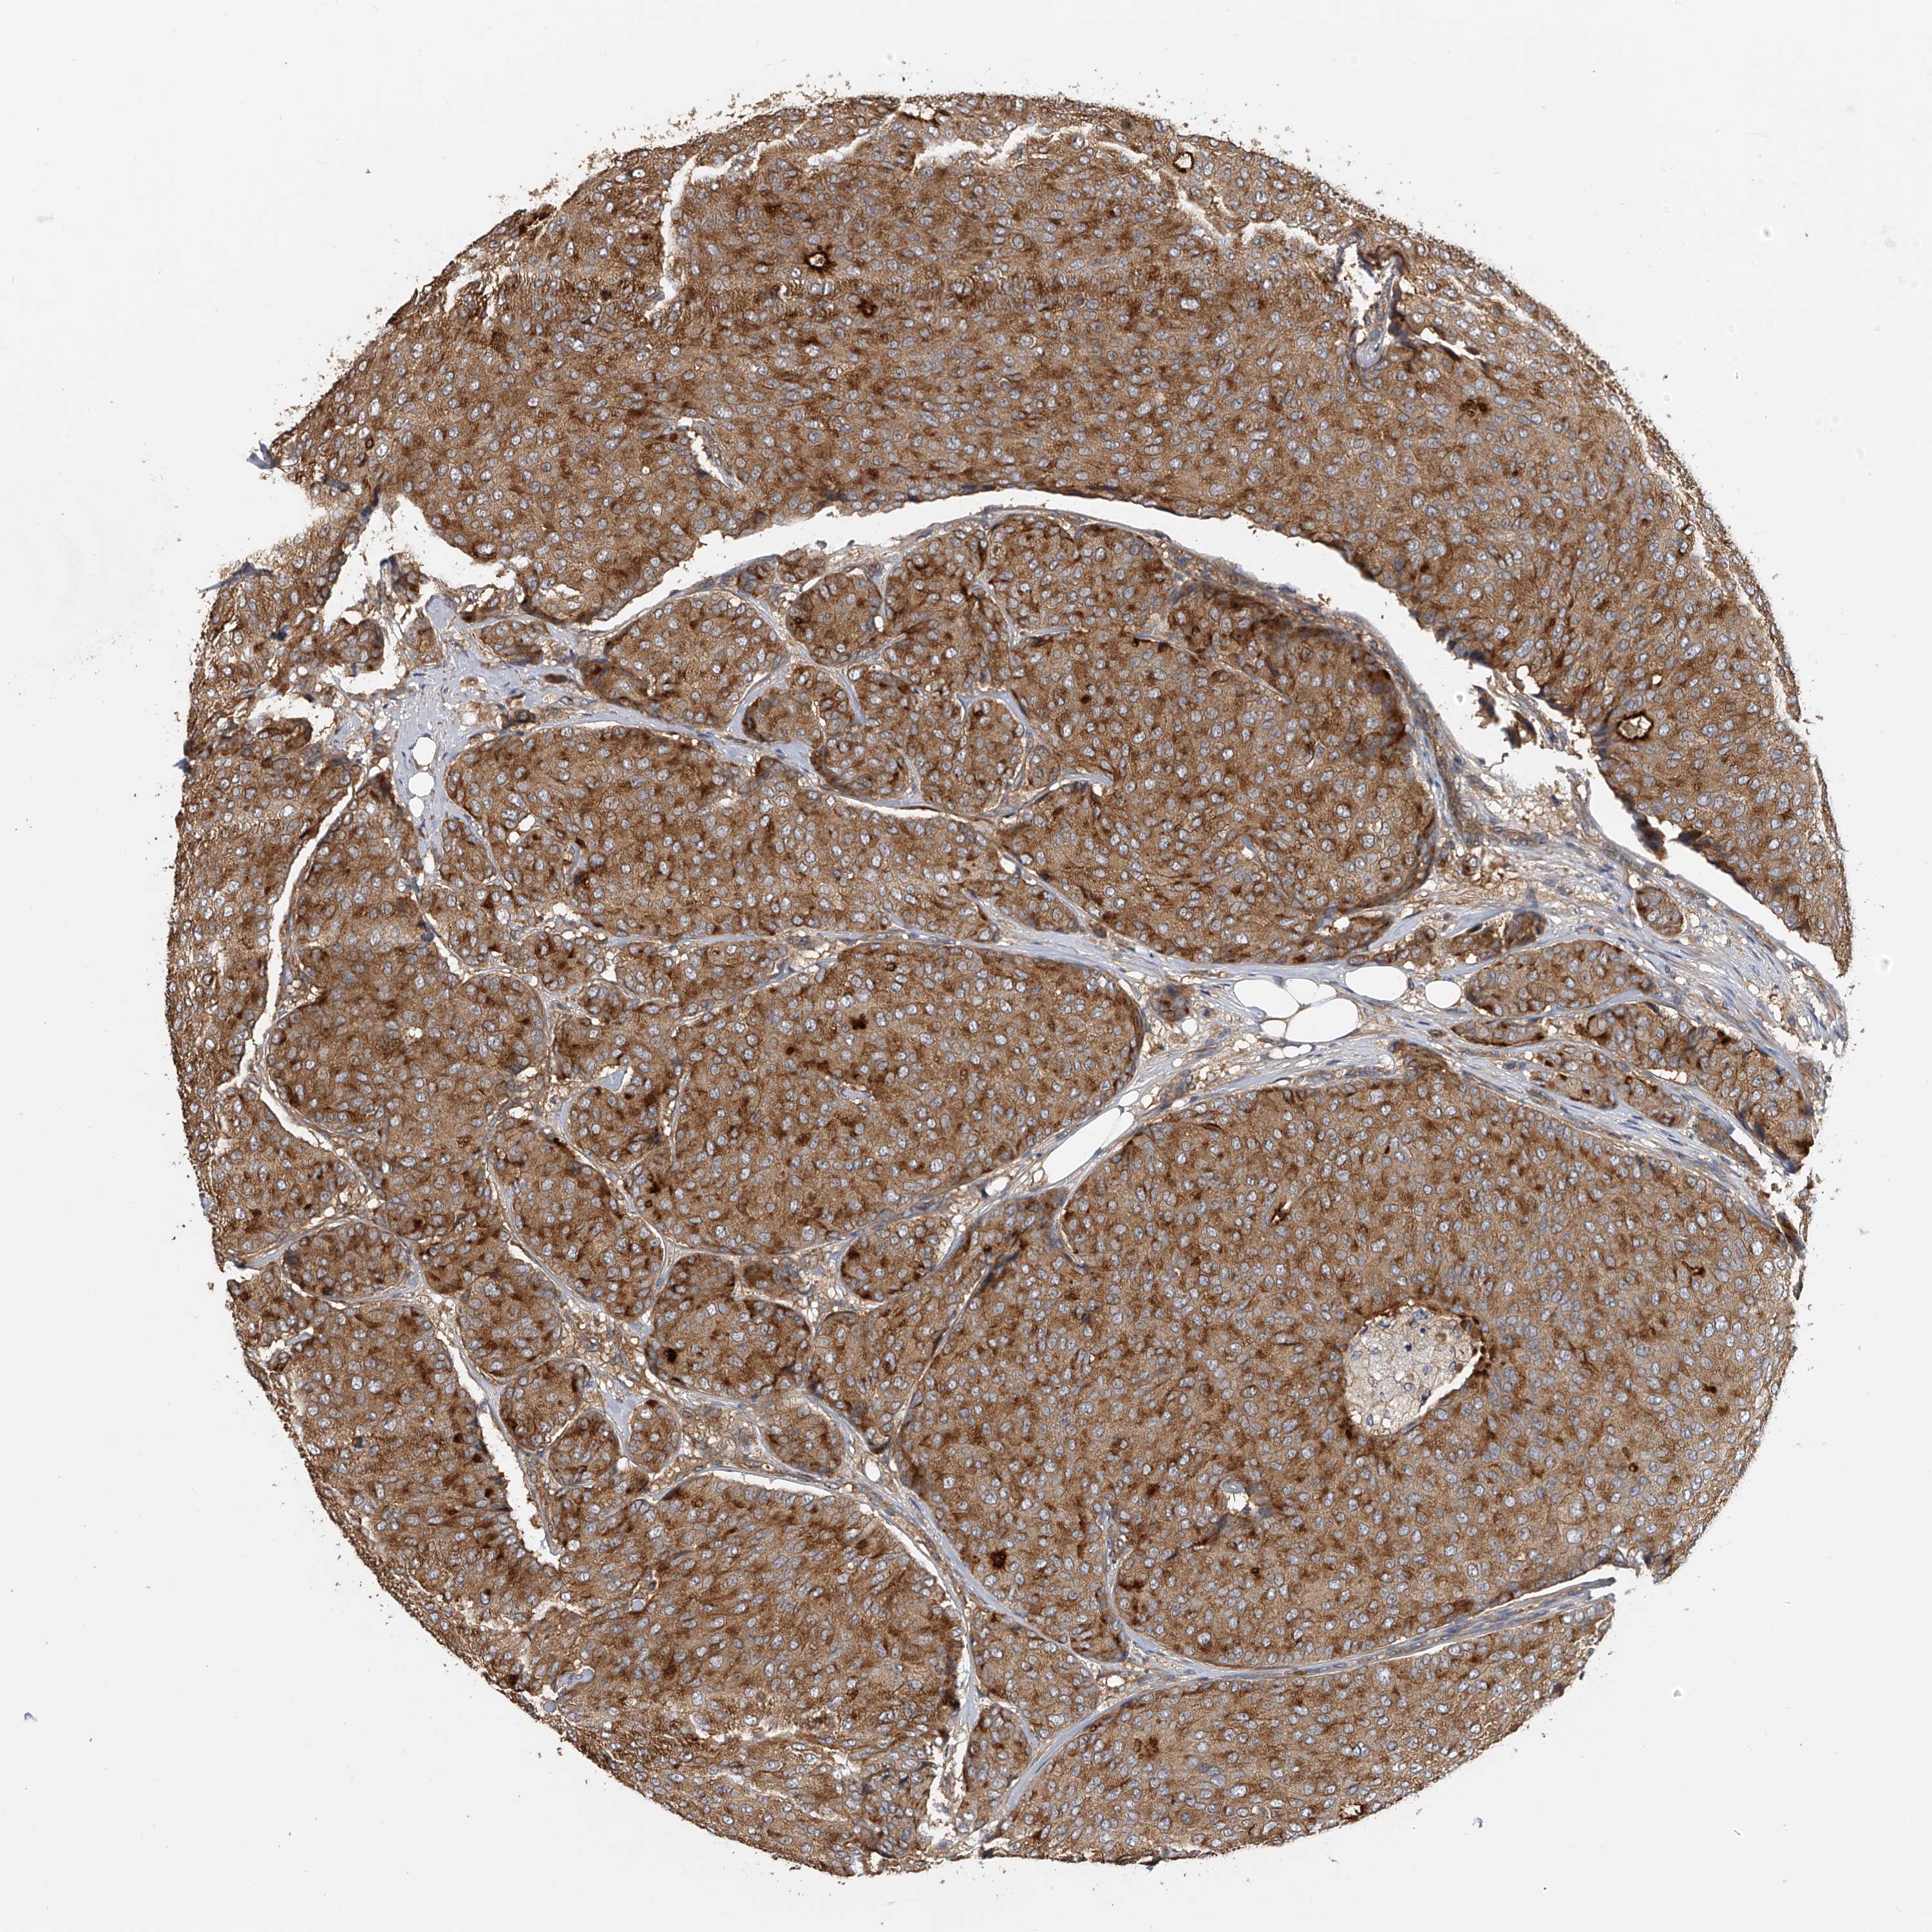

CANCER BREAST CANCER Show tissue menu

BRCA TCGA BRCA VALIDATION PROTEIN EXPRESSION